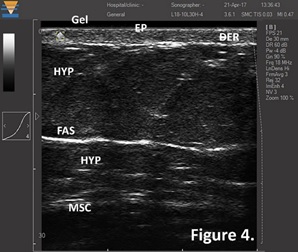

TPM DUB系統15-18 MHz掃描的皮膚圖像,清晰地顯示和測量皮膚全層的影像。Gel-耦合劑,EP-表皮,DER-真皮,HYP-脂肪,FAS-淺筋膜,MSC-肌肉